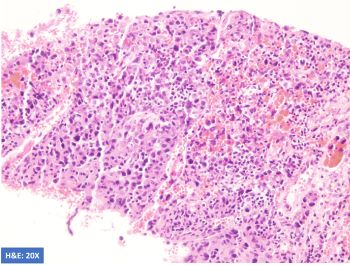

A 52-year-old man with HIV presents with weight loss and supraclavicular mass. Biopsy shows large, atypical cells with the following phenotype: CD45+, CD20-, PAX5 weak, CD3-, CD15-, CD138-, EBER-ISH+. H&E and stains for CD30 and CD79a are shown.

This is a case of EBV-positive diffuse large B-cell lymphoma associated with immune deficiency with an unusual phenotype. B-cell markers are downregulated with negative CD20 and weak expression of PAX5 and CD79a. The unusual phenotype combined with CD30 positivity raises the possibility of Classic Hodgkin lymphoma (CHL). However, the neoplastic cells are positive for CD45 and negative for CD15, making CHL unlikely. Plasmablastic lymphoma was excluded by CD138 negativity.